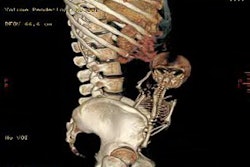

Obesity is a very relative contraindication, and success depends a great deal on its severity. In patients with a body mass index of 40-50, for example, it is definitely easier to image those at the lower end of the scale.

Even for the larger patients, "it is possible with optimal heart rate reduction and the use of dose modulation to obtain adequate image quality by using higher tube current," Weigold said, "but let's not forget the price of a higher dose of radiation. At 17, 21, 25 mSv, we're getting into a range of radiation in which (CTA) is no longer really comparable to plain old invasive coronary angiography. Generally, when you start tipping the scales at a BMI of 40, there are certain situations, I would say, where cardiac CT is pretty much contraindicated."

It certainly can be a waste of scan time and radiation dose when the heart and vessels are poorly visualized and the scan is nondiagnostic. When deciding whether to scan morbidly obese patients, Weigold listed the following co-factors under the "no" category: